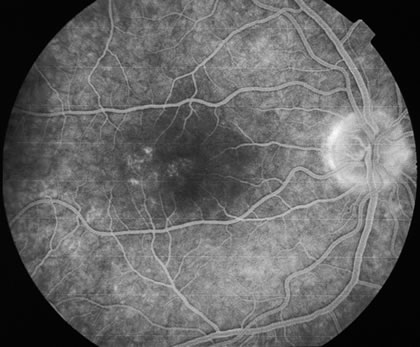

RETINAL FINDINGS

The fundus findings tend to depend on the chronicity of the disease. In new-onset cases, there are just a few choroidal lesions most of which are in the posterior pole. The newer lesions tend to be yellowish-white in coloration and with time they become punched-out. The size of the lesions can be variable ranging from one third to 1 disc diameter in size. They can become confluent and so they may appear larger than the typical size. The newer lesions are associated with visual distortions. Rarely subretinal fluid may be present over fresh choroidal lesions. In addition, choroidal neovascularization may be seen in one third of cases. Subretinal hemorrhage and subretinal fluid should be considered as signs of the development of a possible choroidal neovascular membrane. Retinal phlebitis is rarely present but may be seen as well (Fig. 9).

Fig. 9. A and B. Fundus photographs of the right and left eye showing the classic circular choroidal lesions with marked pigment clumping in a case of multifocal choroiditis.

Fluorescein angiography may show hyperfluorescent spots that increase slightly in the later phases in active lesions. In inactive lesions, these spots become window defects. If there is a choroidal neovascular membrane it is usually seen at the edge of the scar and tends to have classic features. ICG angiography shows hypofluorescent lesions some of which cannot be seen by fundoscopy or by fluorescein angiography. In addition, there may be hypofluorescence surrounding the optic disc in cases of enlarged blind spots in conjunction with multifocal choroiditis.42